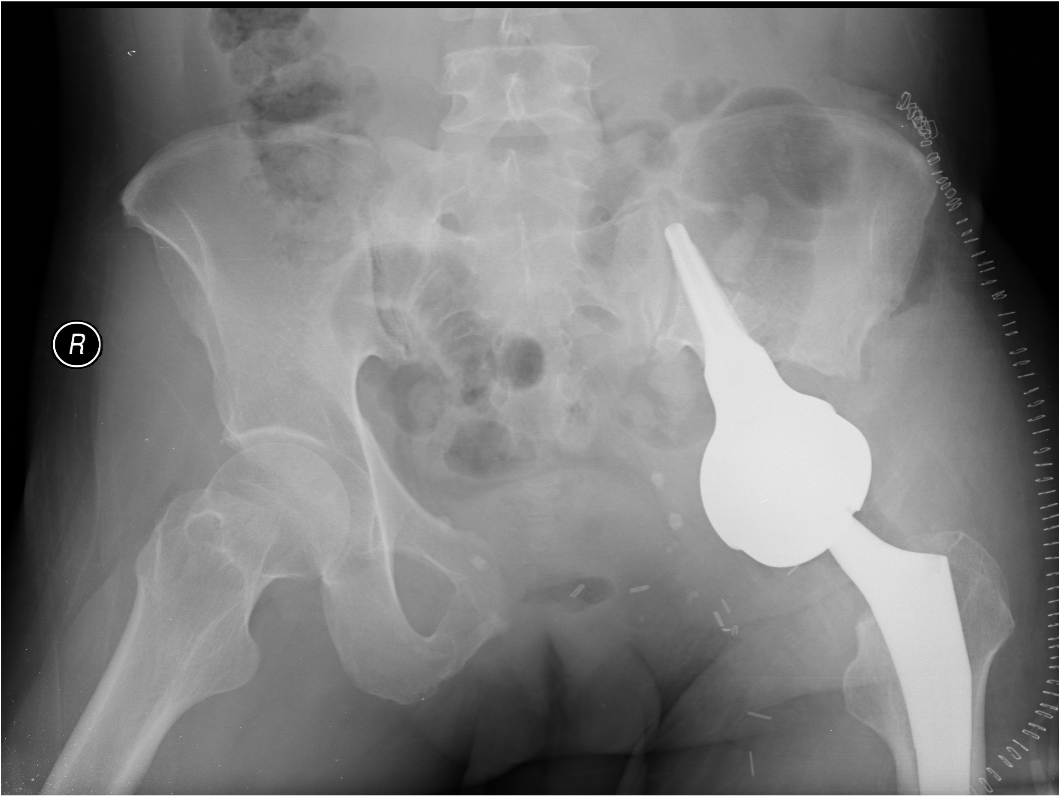

Wide Resection - limb salvage / amputation

2 cm margin of normal tissue if able